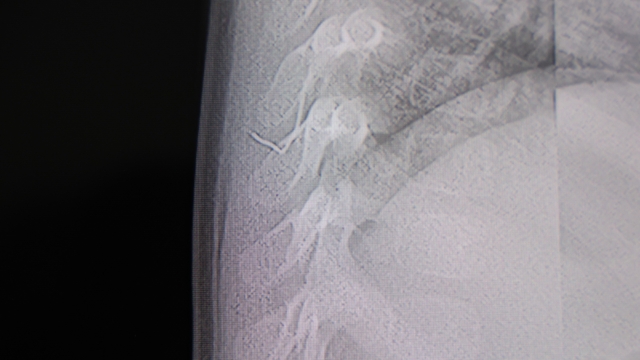

Alınan bilgiye göre, Kahramanmaraş'ta farklı ortopedi, çocuk cerrahisi ve beyin cerrahisi kliniklerine başvurusu yapılan bir yaşındaki bebeğin, sırt bölgesinde yabancı bir cisim olduğu ancak müdahalenin zor olduğu ve 8 yaşına kadar beklenmesi gerektiği bildirildi. Aile, bebekleri için son olarak HG Hospital'e başvurdu. HG Hospital Beyin ve Sinir Cerrahisi Uzmanı Prof. Dr. İdris Altun tarafından yapılan tetkiklerde, yabancı cismin cilt altında, omurilik kanalına yakın bir bölgede olduğu ve akciğer zarına doğru ilerlediği belirlendi. Hasta, genel anesteziye alınmadan, lokal anestezi ve sedasyon eşliğinde ameliyata alındı. Yapılan müdahalede yabancı cisim tamamen çıkarıldı. Çıkarılan cismin, ince zımba teline benzer metal bir tel olduğu ve yaklaşık 2 santimetre uzunluğunda bulunduğu tespit edildi. Hasta, aynı gün taburcu edildi.

Konuya ilişkin açıklama yapan Prof. Dr. İdris Altun, "Sırtında yabancı bir cisim olduğu söylenmiş ancak çıkarılamayacağı ve 8 yaşına kadar beklenmesi gerektiği ifade edilmişti. Bize başvurduğunda yaptığımız tetkiklerde, cilt altında, omurilik kanalına çok yakın ve akciğer zarına doğru ilerleyen bir yabancı cisim tespit ettik. Hastamızı tamamen uyutmadan, lokal anestezi ve sedasyon eşliğinde müdahale ederek lezyonu tamamen çıkardık. Çıkardığımız cismin ince zımba teline benzer, yaklaşık 2 santimetre uzunluğunda metal bir tel olduğunu gördük. Bu yabancı cisim alınmasaydı, bölgede enfeksiyon gelişebilirdi. Enfeksiyon sonucu omurilik kanalında ciddi hasarlar oluşabilir, çocuk büyüdükçe cismin hareket etmesine bağlı olarak omurilikte zedelenmeler meydana gelebilirdi. Ayrıca yana doğru ilerleyerek akciğer zarına ve akciğere batma riski vardı. Bu da enfeksiyona ve ilerleyen süreçte tümörle karışabilecek tablolara neden olabilirdi. Şu an hastamız gayet sağlıklı. Gerekli kontrolleri yaptık ve aynı gün taburcu ettik" dedi.